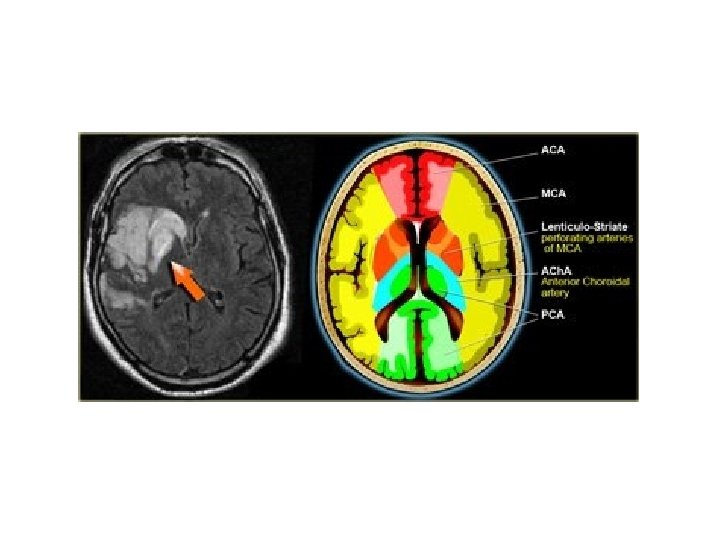

Supplies most of the temporal lobe, anterolateral frontal lobe, and parietal lobe. Perforating branches supply the posterior limb of the internal capsule, part of the head and body of the caudate and globus pallidus.

Unilateral occlusion of MCA at the stem (proximal M 1 segment) results in: • Contralateral hemiplegia affecting face, arm, and leg (lesser). • Homonymous hemianopia - Ipsilateral head/eye deviation. • If on left: global aphasia. • Usually occlusion is embolic in nature - thrombotic occlusion more common in carotids.

Branch of M 1 Segment of MCA. Supplies basal ganglia structures: Part of head and body of caudate, globus pallidus, putamen, and the posterior limb of the internal capsule.